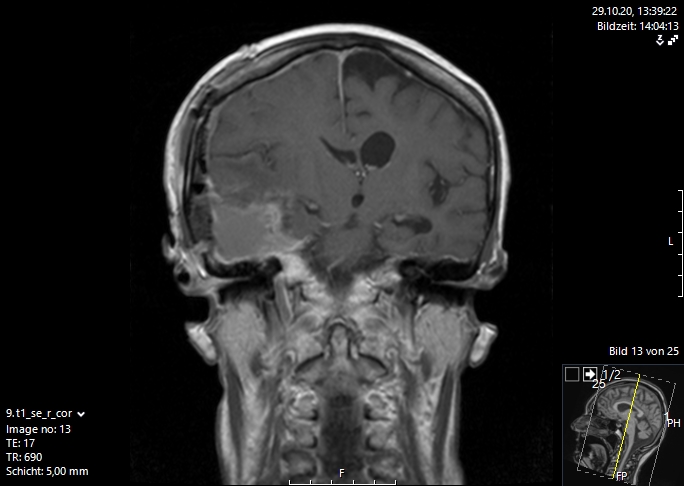

Η μαγνητική τομογραφία εγκεφάλου είναι η μέθοδος εκλογής για την απεικόνιση των εγκεφαλικών μεταστάσεων. Αυτή διενεργείται είτε επί υποψίας αλλοίωσης στο κεντρικό νευρικό σύστημα, λόγω ανάπτυξης μιας νευρολογικής συμπτωματολογίας ή απλά στα πλαίσια του γενικού staging με τακτικές απεικονίσεις στο σώμα και στον εγκέφαλο. Με τη βοήθεια αυτής της απεικονιστικής διαδικασίας μπορεί να γίνει ορατός ο παθολογικά αλλοιωμένος εγκεφαλικός ιστός με τις νεκρώσεις του καθώς και το περιεστιακό εγκεφαλικό οίδημα (συσσώρευση νερού στον εγκέφαλο).

Σήμερα υπάρχουν διάφορες διεγχειρητικές τεχνικές, που μας υποστηρίζουν στο στόχο μας, να αφαιρέσουμε όσο περισσότερο καρκινικό ιστό , αν γίνεται ιστό ακόμα και από την περιοχή γύρω από τον όγκο, που ονομάζουμε διηθητική ζώνη. Μερικές σύγχρονες διεγχειρητικές τεχνικές, είναι η νευροπαρακολούθηση, η νευροπλοήγηση με απεικόνιση των δεσμίδων, η ενδοσκοπική νευροχειρουργική και τα χειρουργεία με ασθενή σε εγρήγορση. Ο συνδυασμός λοιπόν ενός ασφαλούς χειρουργείου με ταυτόχρονη ολική αφαίρεση του όγκου αποτελεί τον στόχο της σύγχρονης χειρουργικής νευρο-ογκολογίας και στην περίπτωση των εγκεφαλικών μεταστάσεων. Οι εικόνες 1 και 2 απεικονίζουν μια ολική εξαίρεση μιας μετάστασης δεξιά κροταφικά. Αυτό είναι σαφέστατα πιο πιθανό να προσφερθεί από ειδήμονες νευροχειρουργούς (Gousias K, 2024) με ειδική εκπαίδευση σε μεγάλα κέντρα, μεγάλη χειρουργική εμπειρία και εξειδίκευση στην χειρουργική των όγκων καθώς και διεθνή αναγνώριση τους. Η επιτροπή Χειρουργικής Νευρο-ογκολογίας της Ευρωπαϊκής Νευροχειρουργικής Εταιρείας δημοσίευσε το προφίλ ενός expert χειρουργού για όγκους εγκεφάλου και νωτιαίου μυελού (Gousias K, 2024).